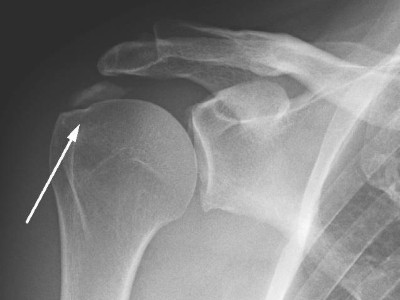

Hund heilt Herrchen von jahrelangem Schmerzproblem

Ausgeprägte rezidivierende Schulterschmerzen mit Kalkdepot oberhalb des Tuberculum majus begleiten einen 39-jährigen Mann über Jahre und trotzen jeglicher Physiotherapie. Dann greift der Dobermann des Patienten auf die rabiatere Tour ein. Und endlich ist Herrchen wieder schmerzfrei.